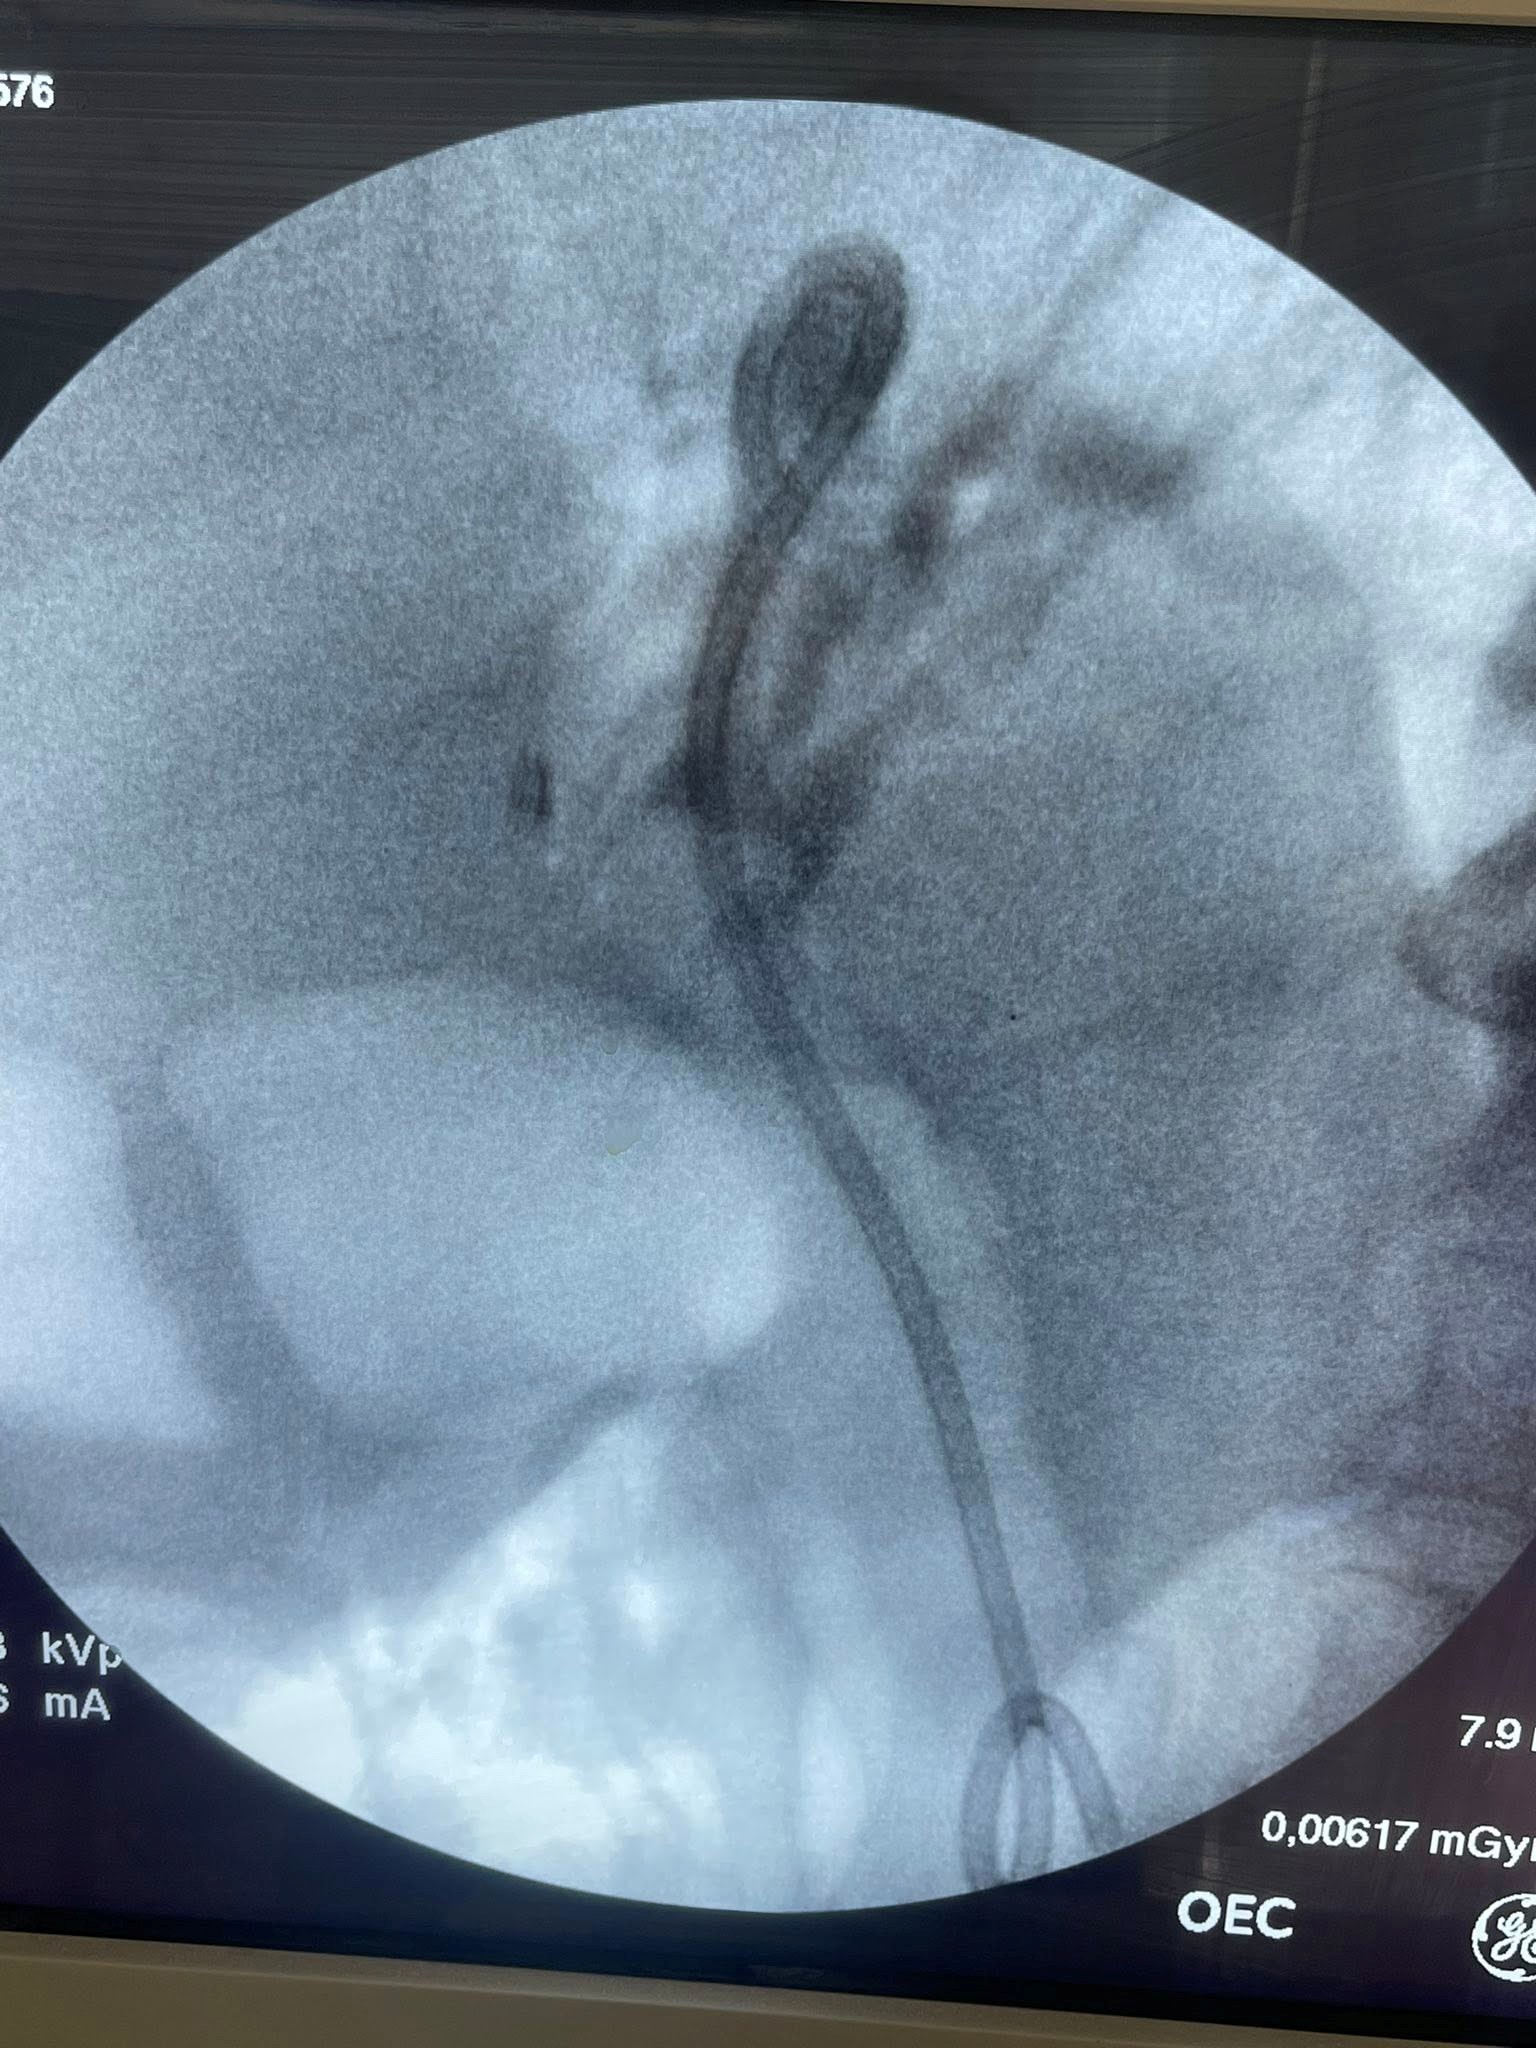

Case Presentation

65 years old female patient underwent lap cholecystectomy 2018 and developed OJ in 2021 ERCP done with insertion of PCSEMS as malignant lower CBD stricture but EUS with FNB revealed benign stricture then patient presented to our Mahalla liver teaching hospital with OJ and cholangitis in 2023 we do ERCP with insertion of FCSEMS in migrated embedded PCSEMS.

Stent in stent technique for removal of PCSEMS

But we failed for removal and transfer the patient for surgical exploration but surgery refused exploration. Patient returned now with severe cholangitis we do ERCP and our plan to put plastic stent inside PCSEMS but the patient was lucky this time

ERCP reveale multiple stones inside stent.

Extraction was done with dormia basket and washing then we use foreign body and fluoroscopy for removal of PCMS.

Insertion of double pigtail stent with good biliary flow.

Fig 1, Fig 2, Fig 3, Fig 4, Fig 5, Fig 6

Figure 1